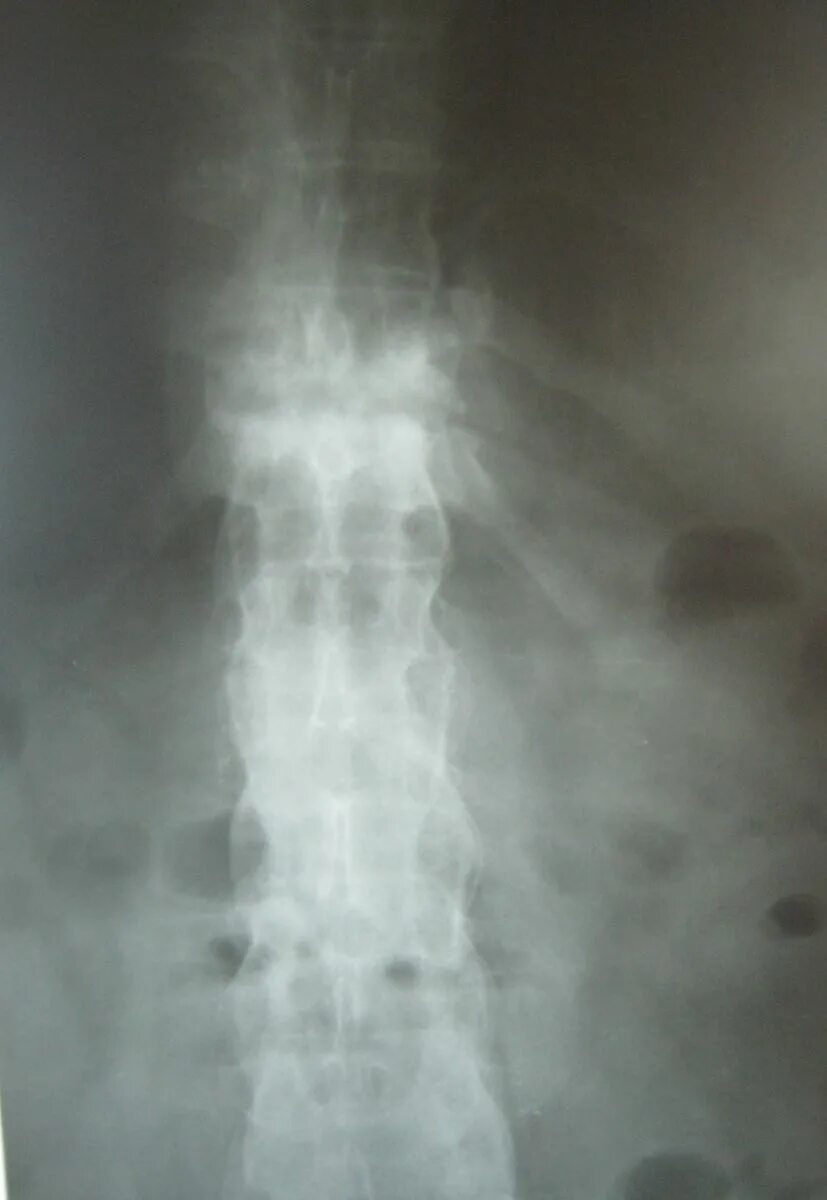

Болезнь бехтерева тазобедренных суставов